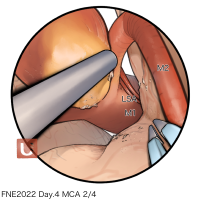

FEN2022シリーズ